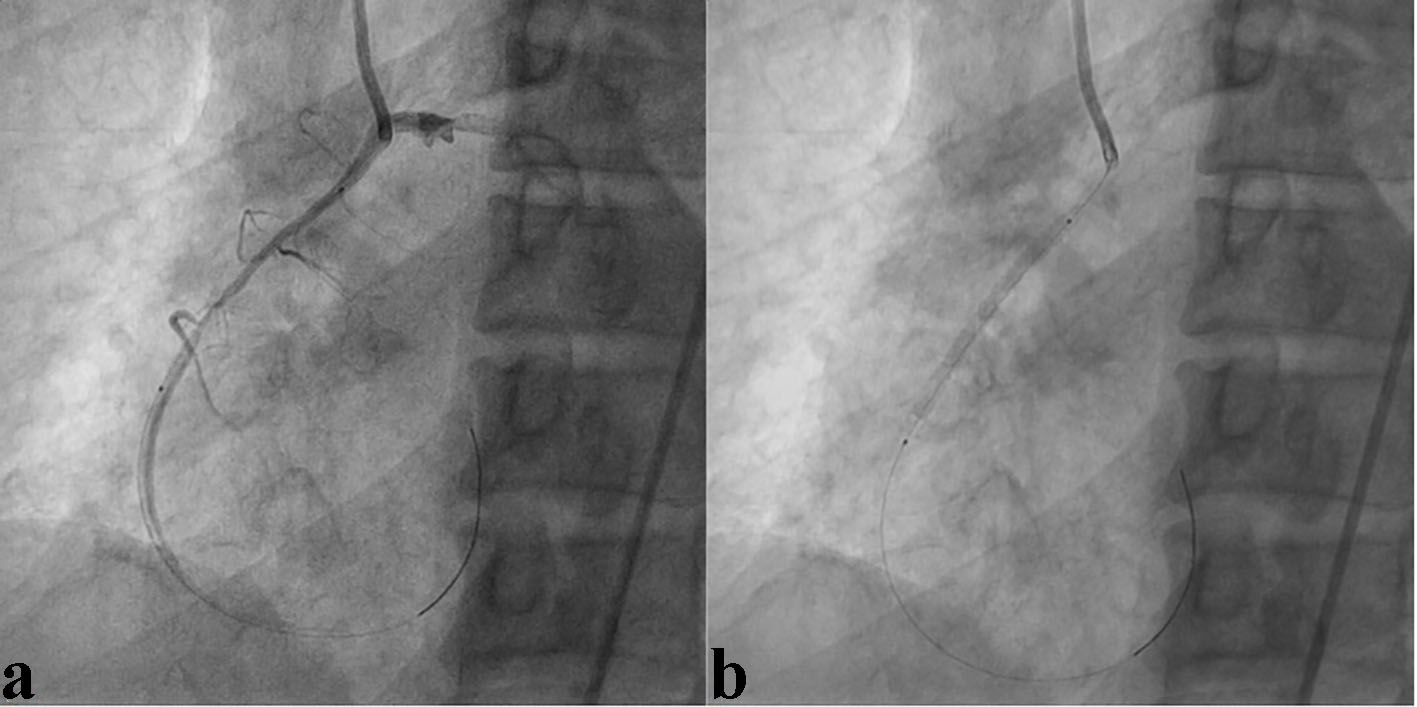

A 69-year-old male smoker with a past history of diabetes mellitus and dyslipidemia presented with retrosternal chest pain and profuse sweating of 12 h duration. His physical examination and biochemistry were all unremarkable. Echocardiography revealed mild hypokinesia in RCA territory with ejection fraction of 49%. Electrocardiogram revealed ST depression and T inversion in II, III, aVF, and V1-V3. In the laboratory analysis, creatine kinase MB (CKMB) was 97 U/L (upper limit 25 U/L), and troponin I was 5.89 ng/mL (upper limit 0.01 ng/mL). In lieu of ongoing angina and high troponin level, he was taken for early invasive coronary intervention through femoral route after proper consent. He was preloaded with prasugrel 60 mg, aspirin 325 mg and atorvastatin 80 mg. The 6-F JR3.5 and JL3.5 Proflo™ diagnostic catheters (Medtronic, USA) were used for catheterization after administering 2,500 U of heparin. Basal angiogram revealed normal left system (left anterior descending artery and left circumflex artery) and ectopic RCA (arising near the root of left main trunk) from left aortic sinus with downward course showing discrete eccentric critical lesion in mid segment with 95% stenosis (Fig. 1a, b). Percutaneous intervention of culprit artery was planned with further administration of 7,000 U of heparin. We tried to cannulate RCA with Judkins left and right (JL, JR), multipurpose (MPA 1, 2), Amplatz left (AL), Amplatz right (AR), and Tiger diagnostic catheter (Terumo, Japan), but failed to cannulate selectively because of its anomalous origin and course. Finally, hockey stick catheter (Boston Scientific, USA) was kept afloat near its ostia by giving a counter clockwise turn to keep it little away from left main trunk (Figs. 2, 3a). We provided a big curve to 0.014" runthrough wire (Terumo, Japan) and by floating in the left sinus, RCA was cannulated and wire was parked distally (Fig. 3a). Lesion was predilated with 2.5 × 10 mm Minitrak balloon (Abott, USA) and stented with 3.5 × 38 Promus Premier stent (Everolimus eluting stent, Boston Scientific, USA) deploying at 10 atm pressure (Figs. 3b, 4a, b) and further postdilated with 3.5 × 10 mm non-compliant Minitrak balloon at 20 atm pressure achieving TIMI III flow (Fig. 5). His symptom and ECG stabilized. Multidetector coronary computer tomography angiogram (MDCT) showed the aberrant RCA arising from left coronary sinus near left main ostium (Fig. 6a, b). He was discharged on the third day with aspirin 150 mg/day, prasugrel 10 mg/day, atorvastatin 80 mg/day, metoprolol 100 mg/day and ramipril 2.5 mg/day. Patient is doing excellent since then with regular follow-up at our institute.

![]() Click for large image | Figure 1. Right coronary artery arising from left aortic sinus near the base of left main trunk showing discrete eccentric critical lesion in mid segment (a). Failure to cannulate right coronary artery with various catheter (b). |